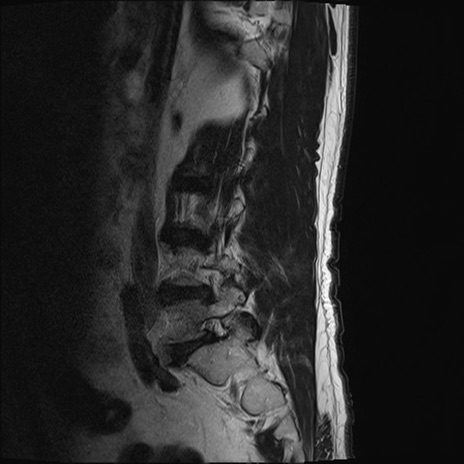

【整形】TIPS症例2 腰椎MRI T2WI(矢状断像)

【症例】70歳代男性

【主訴】左下肢痛

【現病歴】2週間前くらいから腰痛、左下肢痛あり。左臀部から大腿、下腿外側のしびれが常時ある。歩行とともに同部位の痛みあり。

【身体所見】Lasegue70-/60+、Bragard-/±、PTR ±/±、ATR -/-、IP 5/5、TA 5/4、TS 5/5、EHL 右第1足趾なし/3、FHL 5/5、hypersthesia(-)、足背動脈触知良好

異常所見と診断は?